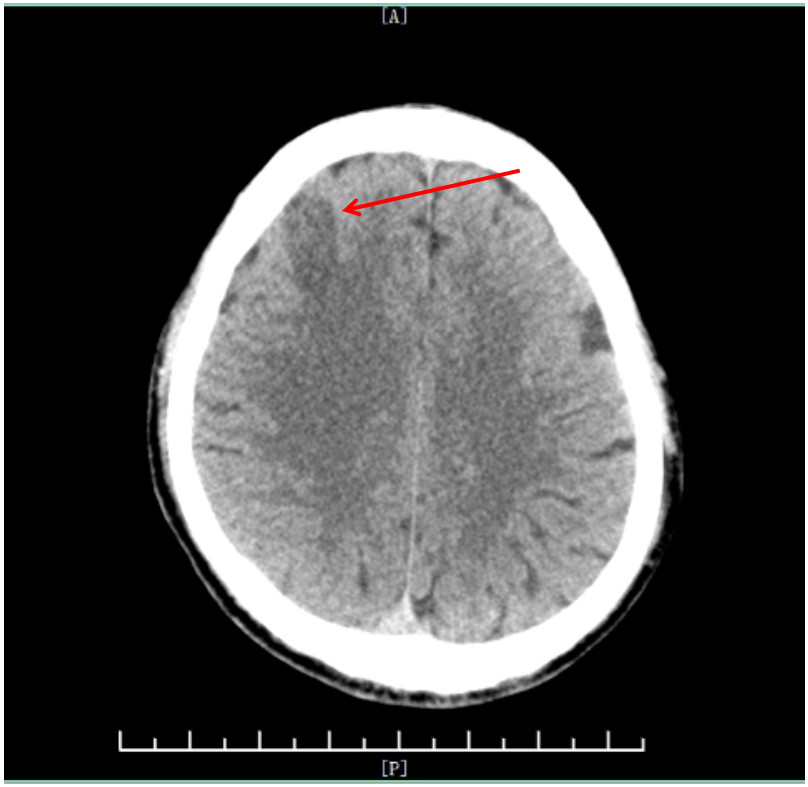

1 病例资料患者56岁男性,因“胸闷、大汗、左侧肢体活动障碍3 h”于2023-09-12入院。入院当日13:20患者突发胸闷大汗、左侧肢体完全不能动弹,15:12至急诊时神志不清。患者既往患高血压病10年,否认烟酒嗜好,否认家族遗传性疾病史。查体:血压120/80 mmHg(1 mmHg=0.133 kPa),神志模糊,两肺无啰音,心率70次/min,心律齐,无杂音,四肢肌力检查不配合,左侧肢体肌张力低,右侧肢体肌张力正常,左侧巴氏征阳性,右侧巴氏征阴性。随机血糖8.34 mmol/L,18导联心电图:窦律,下壁、右室导联ST明显抬高(图 1A、B),心肌酶的肌钙蛋白I:0.038 ng/mL(参考值0~0.034 ng/mL),头颅CT示无脑出血,可见右侧颈内动脉末端高密度征(图 2),提示颈内动脉远端存在血栓。

| 图 2 患者入院头颅CT(红色箭头为右侧颈内动脉末端高密度征) |

术后次日,患者神志转清,生命体征平稳,左侧肌力恢复至4级,复查头颅CT:右侧额叶小片状梗死(图 5)。予拔除气管插管、脱机,观察1 d后转心内科病房。复查肌钙蛋白Ⅰ: 13 ng/mL,超声心动图示(图 6A):左室增大伴左室多壁段收缩活动异常,左室射血分数45%。患者恢复迅速,出院时神志清楚,口齿清晰,左上肢肌力5-级,左下肢肌力5级,住院共11 d。出院诊断:(1)急性下壁、右室心肌梗死、冠心病、心功能KillipI级;(2) CAAs;(3)急性额叶脑梗死;(4)高血压病。出院后给予氯吡格雷75 mg 1次/d、阿司匹林100 mg 1次/d、瑞舒伐他汀10 mg 1次/d,美托洛尔缓释片23.75 mg 1次/d,随访2个月,患者心功能正常(门诊复查心超见图 6B),四肢肌力正常,言语清晰,未遗留明显后遗症。

| 图 5 患者术后头颅CT(红色箭头为右额叶病灶) |